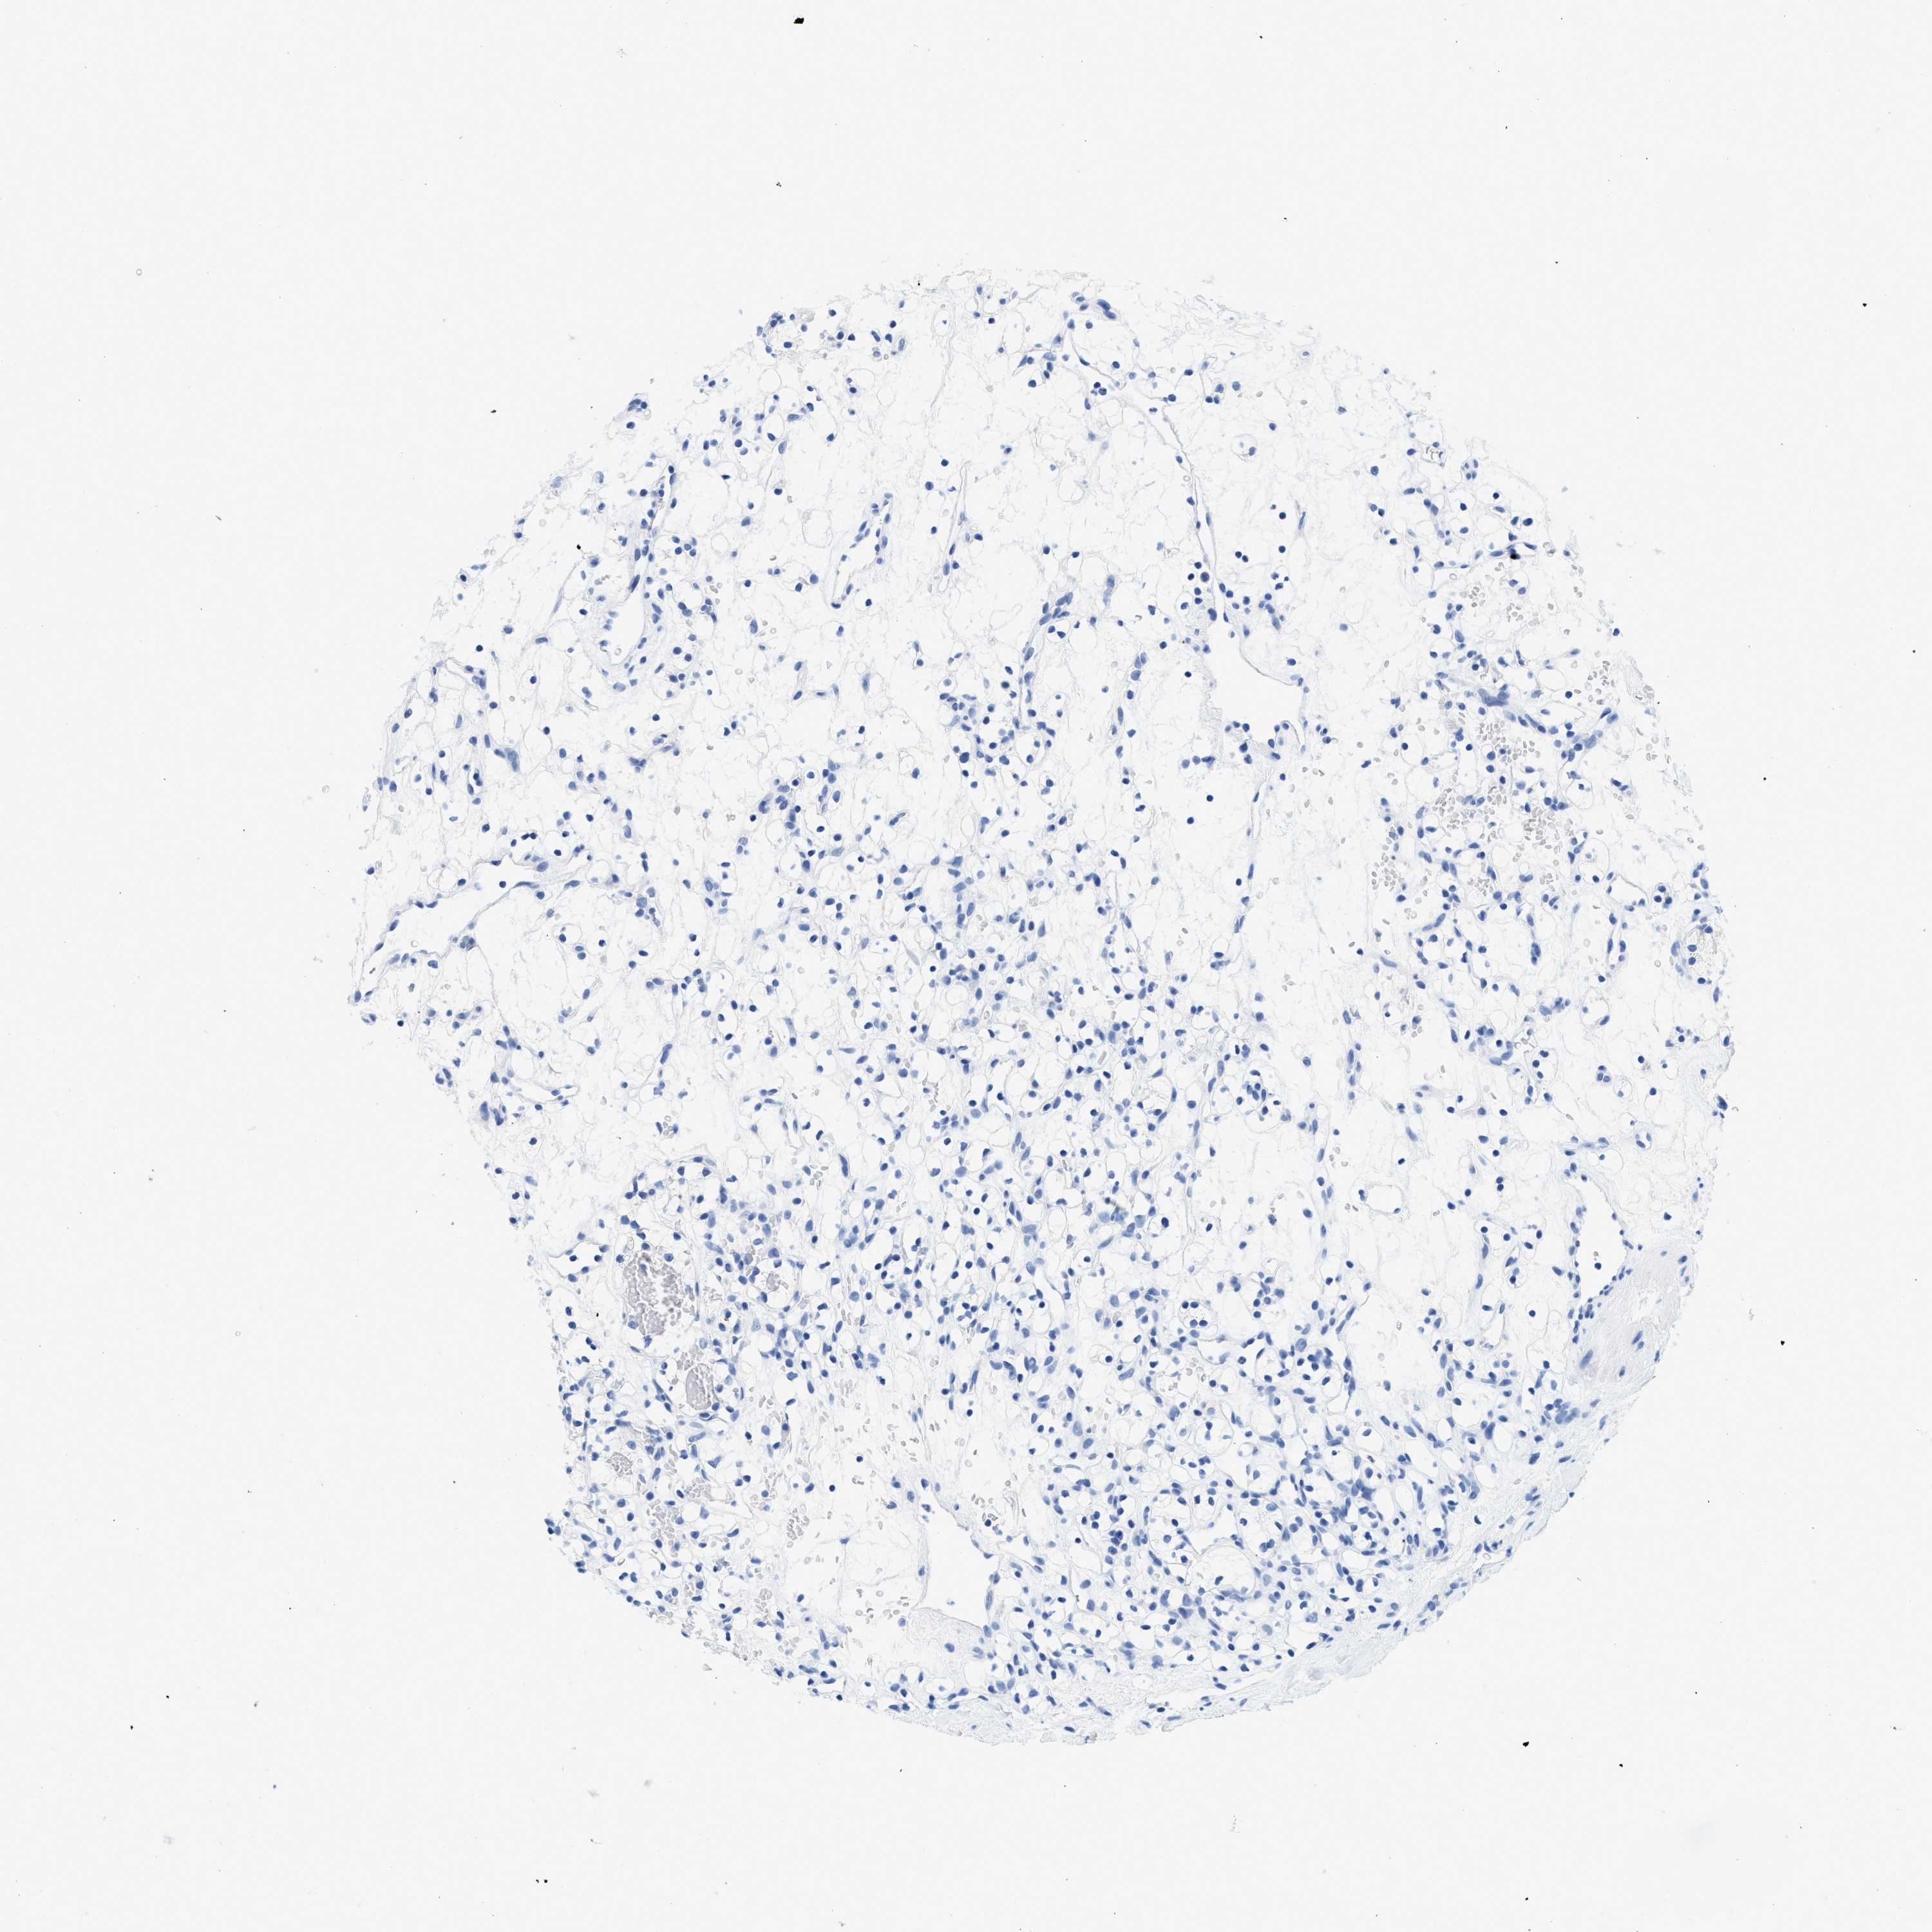

KIDNEY RENAL CLEAR CELL CARCINOMA (VALIDATION) - Interactive survival scatter ploti

The Survival Scatter plot shows the clinical status (i.e. dead or alive) for all individuals in the patient cohort, based on the same data that underlies the corresponding Kaplan-Meier plots. Patients that are alive at last time for follow-up are shown in blue and patients who have died during the study are shown in red.

The x-axis shows the expression levels (FPKM) of the investigated gene in the tumor tissue at the time of diagnosis. The y-axis shows the follow-up time after diagnosis (years). Both axes are complimented with kernel density curves demonstrating the data density over the axes. The top density plot shows the expression levels (FPKM) distribution among dead (red) and alive patients (blue). The right density plot shows the data density of the survived years of dead patients with high and low expression levels respectively, stratified using the cutoff indicated by the vertical dashed line through the Survival Scatter plot. This cutoff is automatically defined based on the FPKM cutoff that minimizes the p-score. The cutoff can be changed by dragging the vertical line or by entering a cutoff value in the square labeled "Current cut-off".

Under the Survival Scatter plot the p-score landscape (black curve; left axis) is shown together with dead median separation (red curve; right axis). Dead median separation is the difference in median mRNA expression between patients who have died with high and low expression, respectively. It is calculated as follows: median FPKM expression of dead patients with high expression - median FPKM expression of dead patients with low expression. This is intended to aid the user in visually exploring custom cutoffs and the associated p-scores and dead median separation.

Individual patient data is displayed and can be filtered by clicking on one or more of the category buttons on the top of the page. Categories describing expression level and patient information include: high, low, alive, dead, female, male and tumor stages. The scale of the x-axis can be toggled between linear and log-scale by clicking on the "x log" button. Mouse-over function shows TCGA ID, patient information and mRNA expression (FPKM) for each patient.

& Survival analysisi

Kaplan-Meier plots summarize results from analysis of correlation between mRNA expression level and patient survival. Patients were divided based on level of expression into one of the two groups "low" (under cut off) or "high" (over cut off). X-axis shows time for survival (years) and y-axis shows the probability of survival, where 1.0 corresponds to 100 percent.

GSN is validated prognostic, high expression is favorable in Kidney Renal Clear Cell Carcinoma (validation)

Best expression cut offi

Based on the FPKM value of each gene, patients were classified into two groups and association between prognosis (survival) and gene expression (FPKM) was examined. The best expression cut-off refers the FPKM value that yields maximal difference with regard to survival between the two groups at the lowest log-rank P-value. Best expression cut-off was selected based on survival analysis .

When clicking on this number, the vertical dashed line indicating cut-off, the interactive survival plot, and the Kaplan-Meier curve will be adjusted to show results based on the best expression cut-off.

: 192.95

TCGA RNA samplesi

RNA-seq data is reported as average FPKM (number Fragments Per Kilobase of exon per Million reads), generated by the The Cancer Genome Atlas (TCGA) .

Normal distribution across the dataset is visualized with box plots, shown as median and 25th and 75th percentiles. Points are displayed as outliers if they are above or below 1.5 times the interquartile range. FPKM values of the individual samples are presented next to the box plot.

Average pTPM 309.2

Number of samples 100